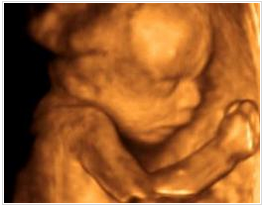

檢查室里面布置的很溫馨,醫(yī)生微笑著接待了我,讓我躺在軟軟的檢查床上,接下來就是期待已久的時(shí)刻了,醫(yī)生先在我肚子上抹了種滑溜溜的東西,然后用掃描儀在肚皮上滾來滾去,奇跡出現(xiàn)啦!屏幕上出現(xiàn)了小寶寶的影像,瞬間覺得奇妙又幸福。出乎我的意料的是畫面十分清晰,不用醫(yī)生解說,我這個門外漢也可以看清楚寶寶的樣子,醫(yī)生說這是從美囯引進(jìn)的ge四維彩超,能夠多角度、全方位的觀察到腹中寶寶的狀態(tài)。

可是寶寶似乎不怎么配合我們,舉著小手擋在臉前,還留給了我們一個美麗的側(cè)臉,這是猶抱琵琶半遮面的節(jié)奏么?看來我家小寶貝兒是個害羞的娃呀。我跟寶寶輕輕說著話,叫它乖寶寶,可是寶寶還是一副我不理你的樣子,這時(shí)醫(yī)生用手輕輕捏了下我的肚子,寶寶這才把臉轉(zhuǎn)了過來,我終于看到寶寶的正面了,簡直是和它媽媽一樣美呆了,嘻嘻。

醫(yī)生一邊給醫(yī)生助理報(bào)數(shù)據(jù),一邊耐心的為我講解,哪里是寶寶的手啊腳啊,之后我們又聽到了臍血流和胎心音,醫(yī)生說寶寶的身體很健康,一切都正常,我這才放心下來。整個四維彩超檢查過程大約持續(xù)1個小時(shí),可我仍覺得意猶未盡,期間還把寶寶的萌照拍了下來,是不是很可愛呢?

做四維彩超所看到的胎兒在宮內(nèi)的情況